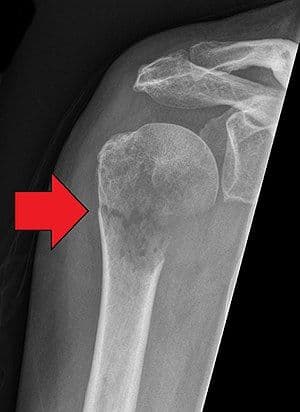

Impacted Fracture - एखादे हाड तुटते तेव्हा त्या हाडाचा हिस्सा दुसऱ्या हाडांमध्ये घुसण्याची स्थिती.